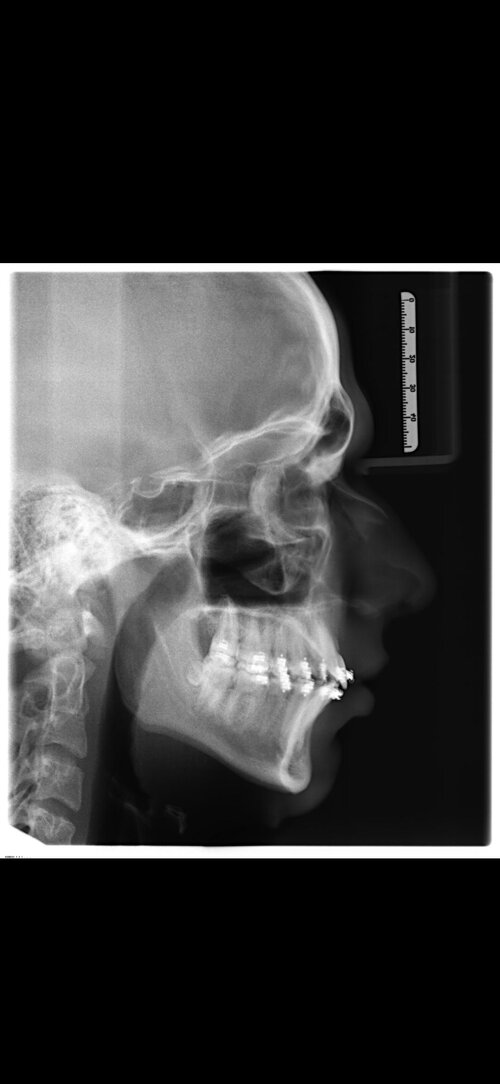

I'm getting bimax + genioplasty and a slight rotation performed by Dr Dr Kater (Germany). I'm scared that i'll be disappointed due to having too high expectations.

My occlusion is already Class 1 (pretty much perfect due to orthodontics) i have a very recessed chin which will be fixed by the genioplasty, but the advancement of the jaws won't be anything too crazy. These are some pictures, how much of an ascension can i expect? He's a rather conservative surgeon with very much experience, but he knows that i wan't a strong projected chin. So what expectations can i have?

My occlusion is already Class 1 (pretty much perfect due to orthodontics) i have a very recessed chin which will be fixed by the genioplasty, but the advancement of the jaws won't be anything too crazy. These are some pictures, how much of an ascension can i expect? He's a rather conservative surgeon with very much experience, but he knows that i wan't a strong projected chin. So what expectations can i have?